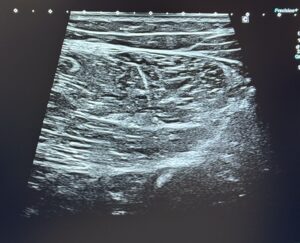

ハムストリングスの超音波エコーでは坐骨神経を中心に配置するのが基本です。

基本ビューでは

画面右(外側):大腿二頭筋長頭

画面左(内側):半腱様筋

その間には共同腱が位置しており、大腿二頭筋長頭、半腱様筋、半膜様筋の一部が坐骨結節に付着する際に形成される腱性構造で、肉離れの好発部位のひとつでもあります。

この部位での損傷は修復に時間を要するため、正確なエコー評価が不可欠です。